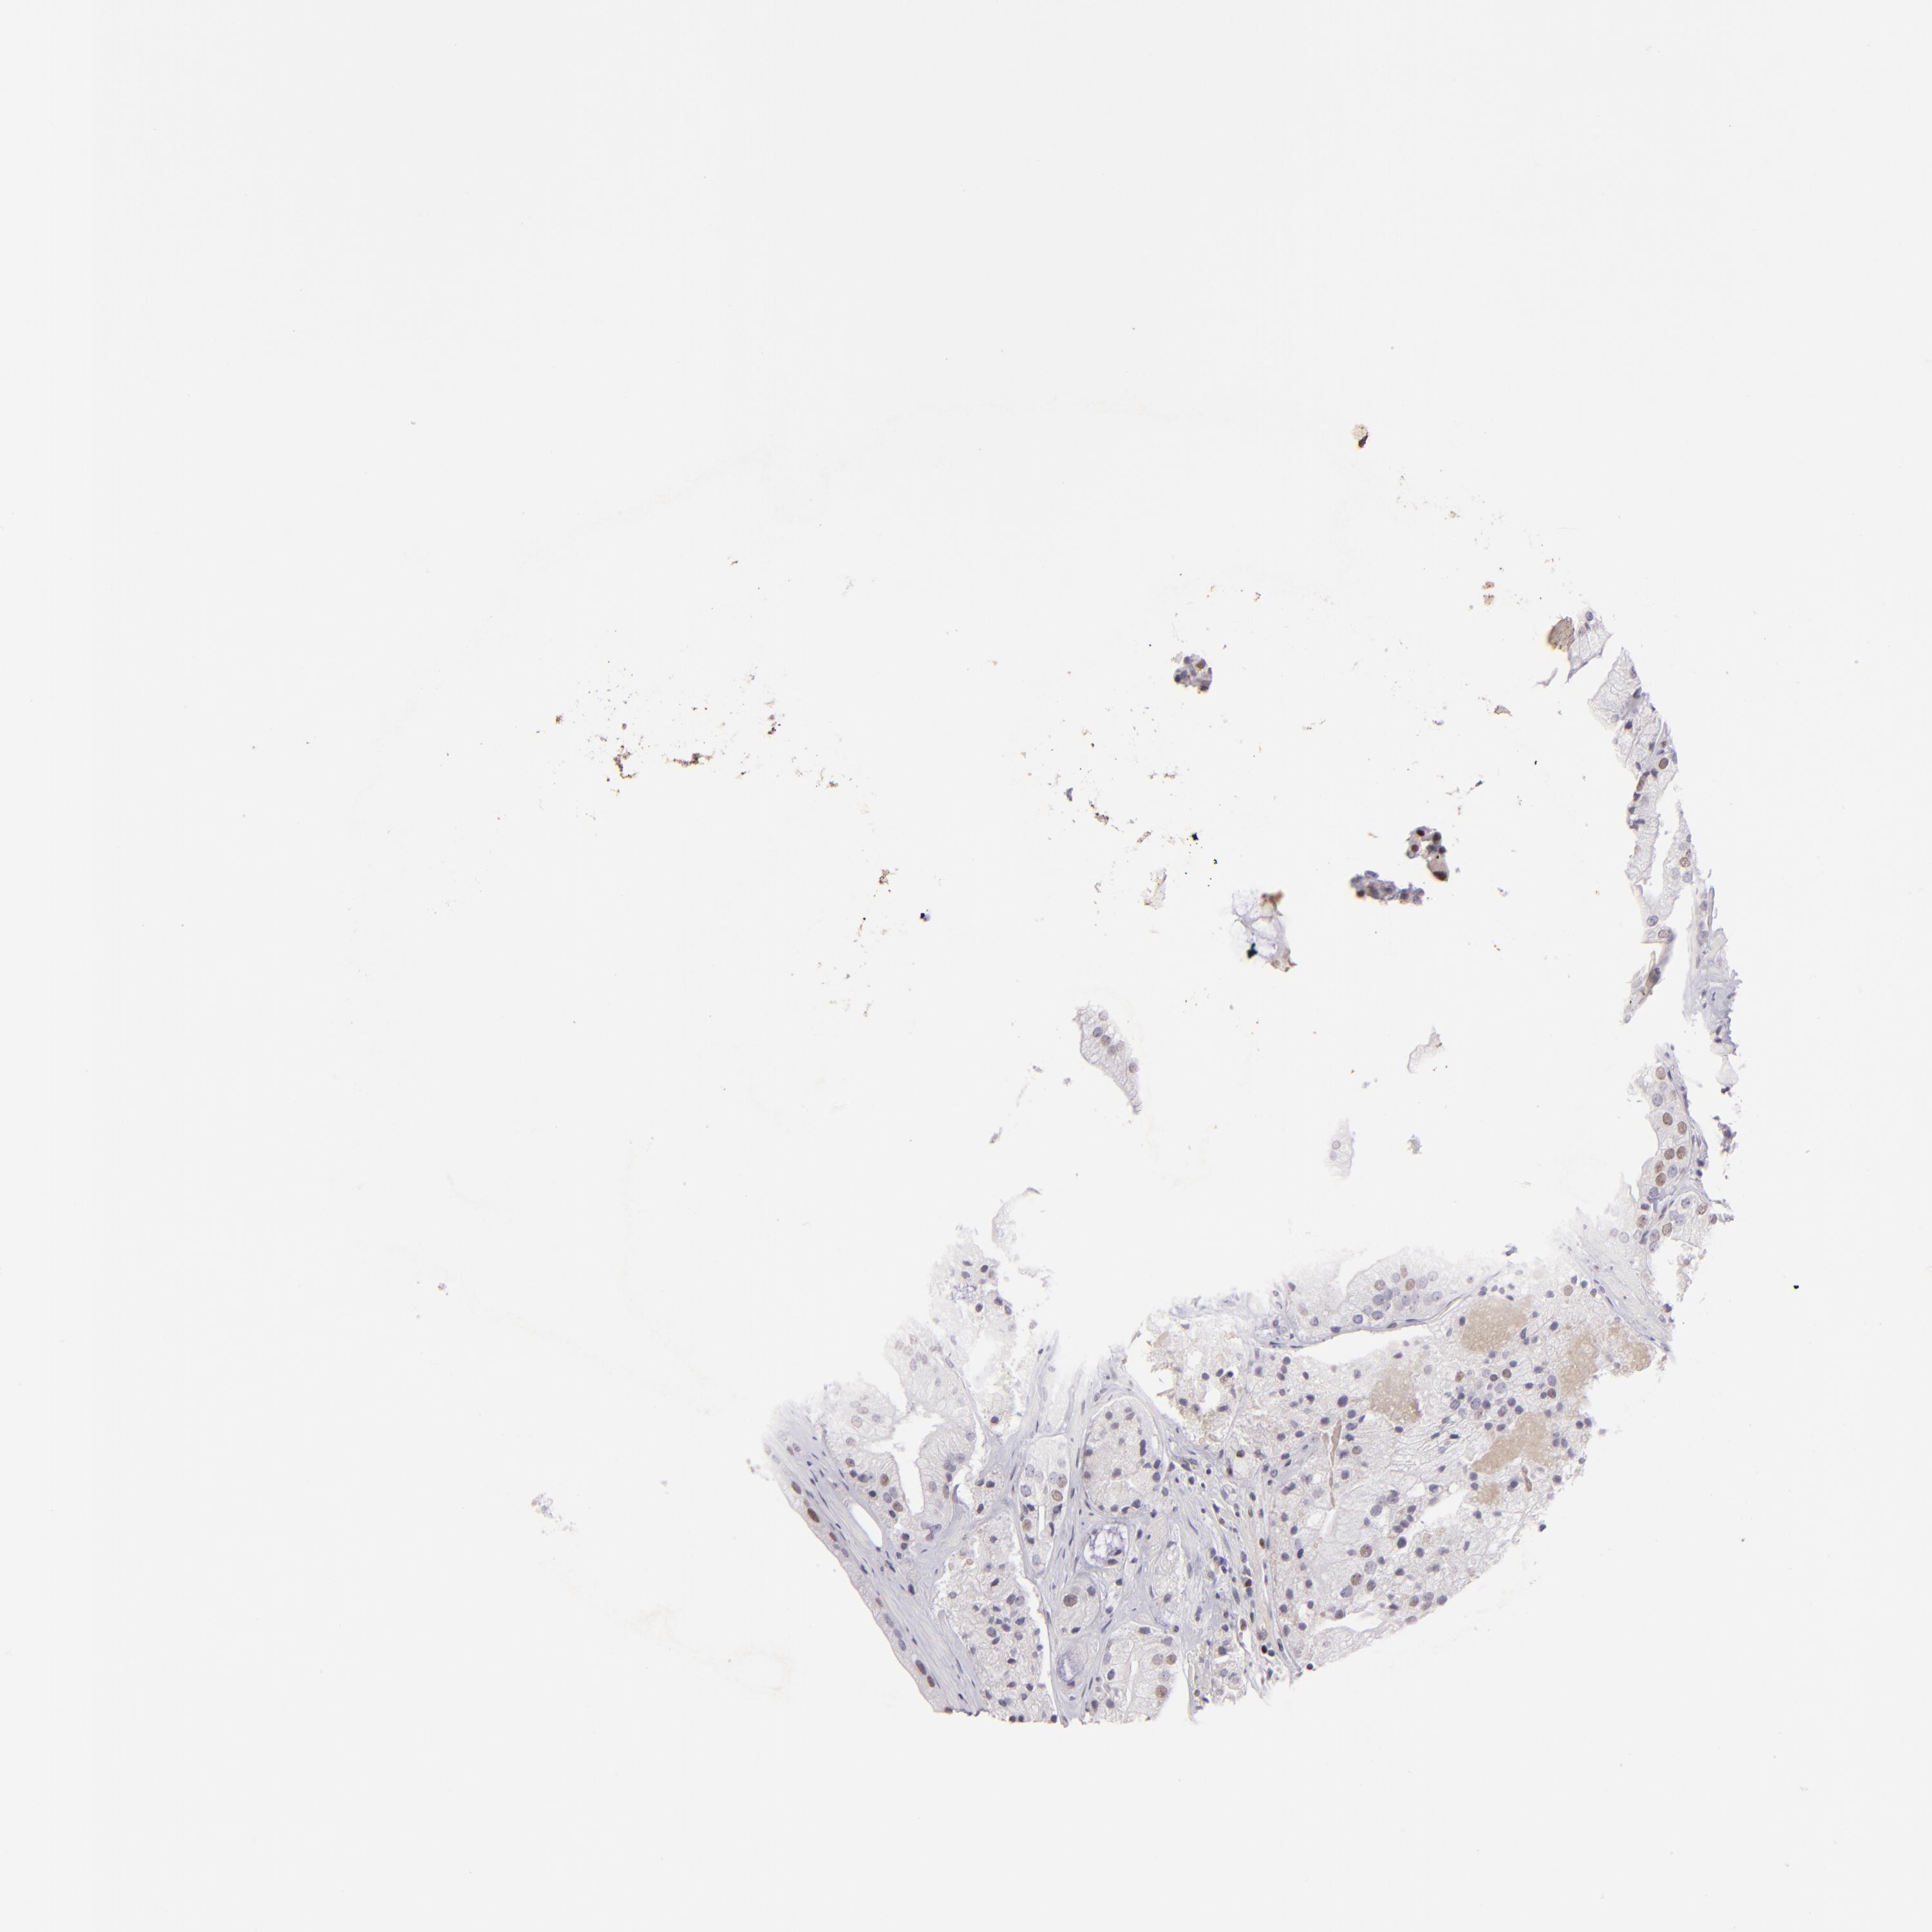

PROSTATE CANCER - Protein expressioni

A mouse-over function shows sample information and annotation data. Click on an image to view it in a full screen mode. Samples can be filtered based on level of antibody staining by selecting one or several of the following categories: high, medium, low and not detected. The assay and annotation is described here.

Antibody stainingi

Antibody staining in the annotated cell types in the current human tissue is reported as not detected, low, medium, or high, based on conventional immunohistochemistry profiling in selected tissues. This score is based on the combination of the staining intensity and fraction of stained cells.

Each image is clickable and will lead to virtual microscopy that enables deeper exploration of all samples and also displays staining intensity scores, fraction scores and subcellular localization as well as patient and tissue information for each sample.

Antibody HPA064323

Antibody CAB002608

Staining

High

Medium

Low

Not detected

Intensity

Strong

Moderate

Weak

Negative

Quantity

>75%

75%-25%

<25%

None

Location

Nuclear

Cytoplasmic/membranous

Cytoplasmic/membranous,nuclear

Adenocarcinoma, High grade

Adenocarcinoma, Low grade

Adenocarcinoma, Medium grade